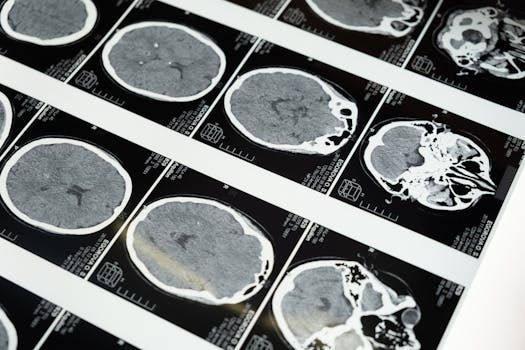

Prema riječima dr. Borovića, većina srčanih udara i moždanih poremećaja se dešava u jutarnjim satima, kada je naše tijelo često dehidrirano. Ovaj nedostatak tečnosti može biti opasan, a kafa, koja je diuretik, dodatno pogoršava situaciju jer izbacuje više tečnosti iz tijela nego što je unosi. Naime, ljudsko tijelo se tokom noći ne unosi tečnost, a jutarnja šoljica kafe može izgledati kao brz način za buđenje. Međutim, u stvarnosti, kafa može postati potencijalna prijetnja, posebno za osobe koje se suočavaju sa stresom ili anksioznošću. Naime, kofein može pojačati osjećaj nelagode i stresa, što može dovesti do ozbiljnih zdravstvenih problema. U tom smislu, postavlja se pitanje: da li smo svjesni koliko malo vode pijemo i koliko je to važno za naše cjelokupno zdravlje?